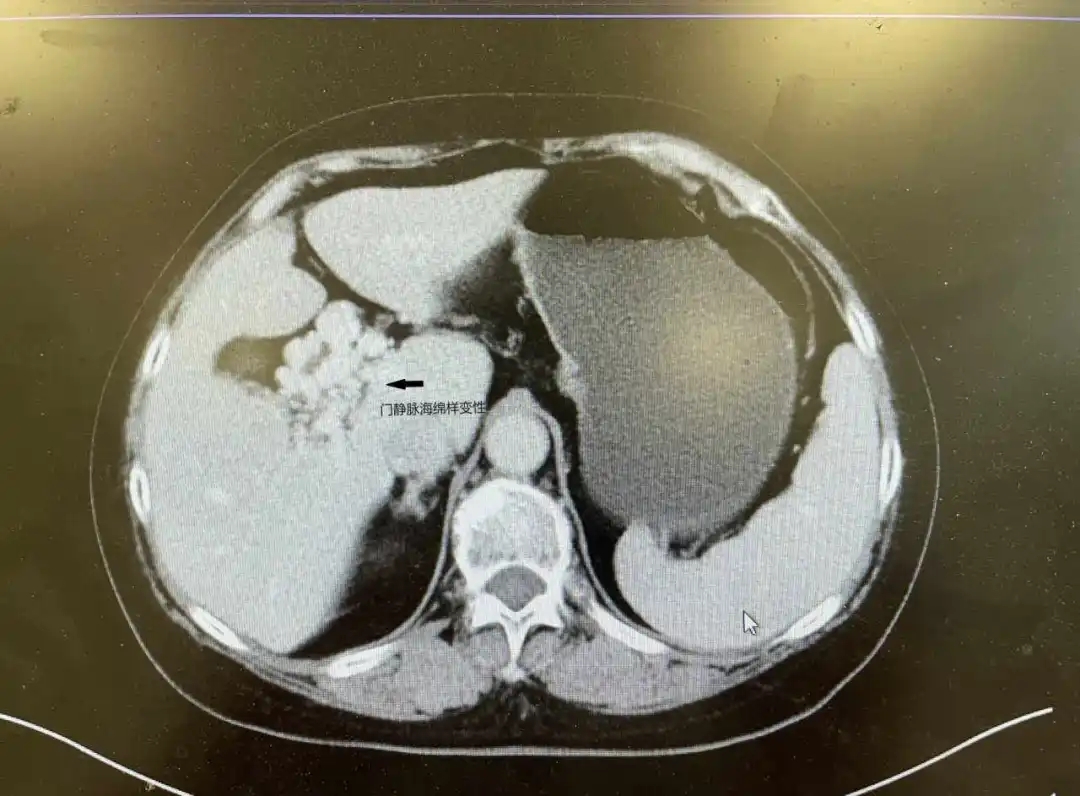

门静脉海绵样变性 (CTPV)是指各种原因所致的门静脉主干和/或它的分支完全或部分阻塞后十二指肠韧带内形成海绵状扭曲的侧枝血管网,可形成门-门分流及门-体分流,使门静脉再通所致的一种代偿性病变,由于大体标本切面呈海绵状血管瘤样改变,故称为海绵样变性。部分CTPV分型可能在肝门部及胆囊床处形成蜂窝状血管团,在胆囊切除手术过程中,如血管损伤则会导致大出血,危及生命,因此确定血管病变的范围极其重要。

术前讨论中,刘润田会同科室王文耀主任、张鸿飞、闫长青等多位专家仔细查阅了患者的增强CT,并针对胆囊区域的门静脉侧枝制定处理方案。针对术中可能面临的大出血,术前请麻醉科张山教授会诊,制定了个体化的麻醉方法及出血处理应急预案。